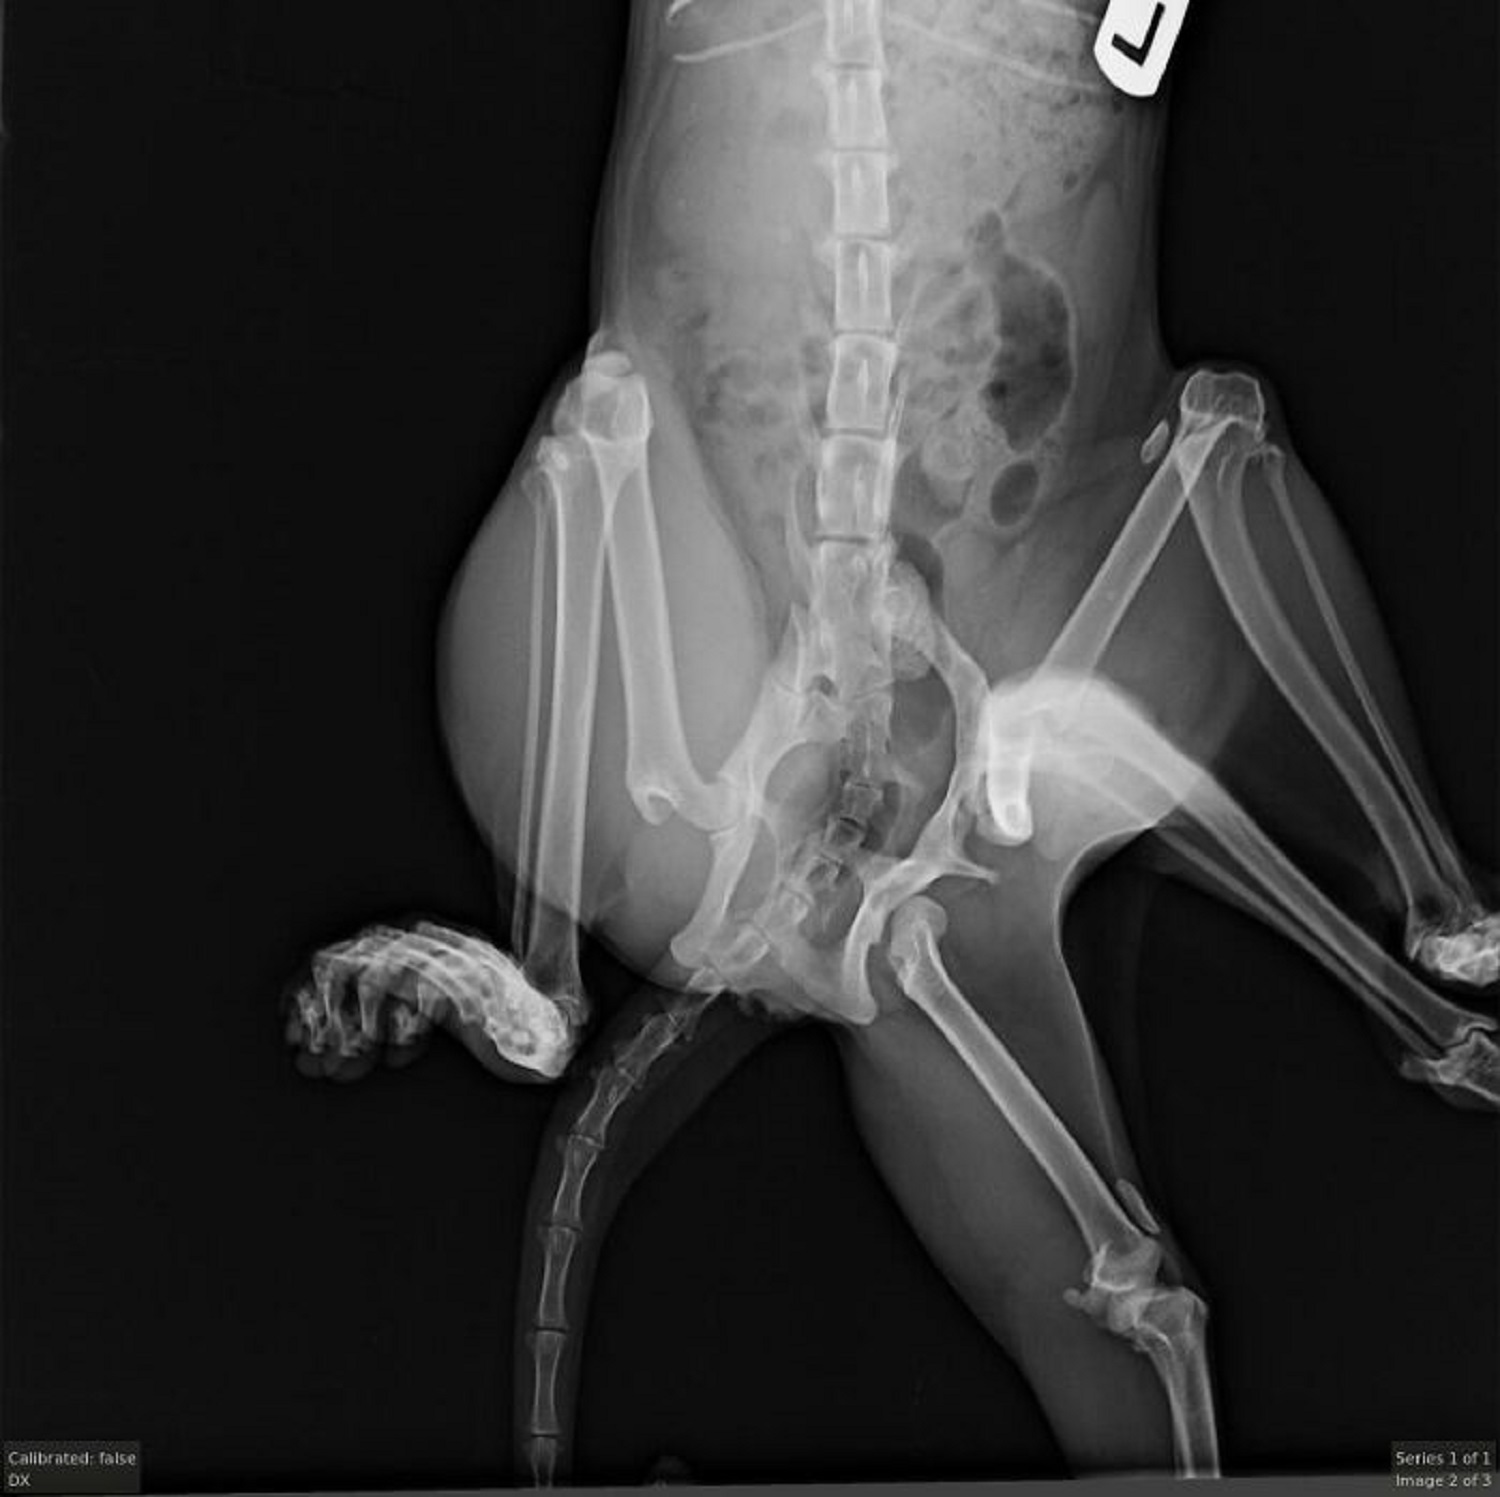

Вони відвезли Бітсі до ветеринарної клініки "Windermere Veterinary Hospital", де їй зробили рентген і вирішили: потрібна складна хірургічна операція. Завдяки пожертвам небайдужих людей було зібрано кошти на втручання, під час якого ветеринари видалили додаткові кінцівки та таз.

Вона виглядала наче з фільму жахів: як хірурги врятували унікальну шестилапу кішкуТаз Бітсі був суцільною аномалією (фото: instagram.com/furgetmenotyeg)